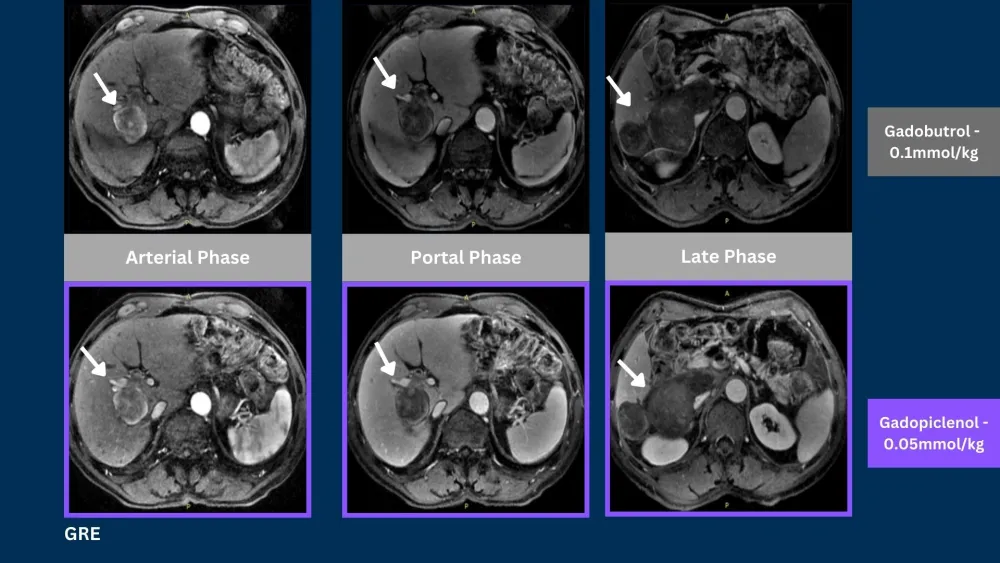

Phase III clinical trials, in CNS and Body, demonstrated that gadopiclenol at a dose of 0.05 mmol/kg was noninferior to gadobutrol at a dose of 0.1 mmol/kg in terms of lesion visualization.5,6

Case 169 year old male2

Liver Cancer

SE = Spin Echo, GRE = Gradient Echo, 3DGRE = 3D Gradient Echo, TSE = Turbo Spin Echo

Phase III PROMISE trial in the body demonstrated that gadopiclenol at a dose of 0.05 mmol/kg was noninferior to gadobutrol at a dose of 0.1 mmol/kg in terms of lesion visualization.6